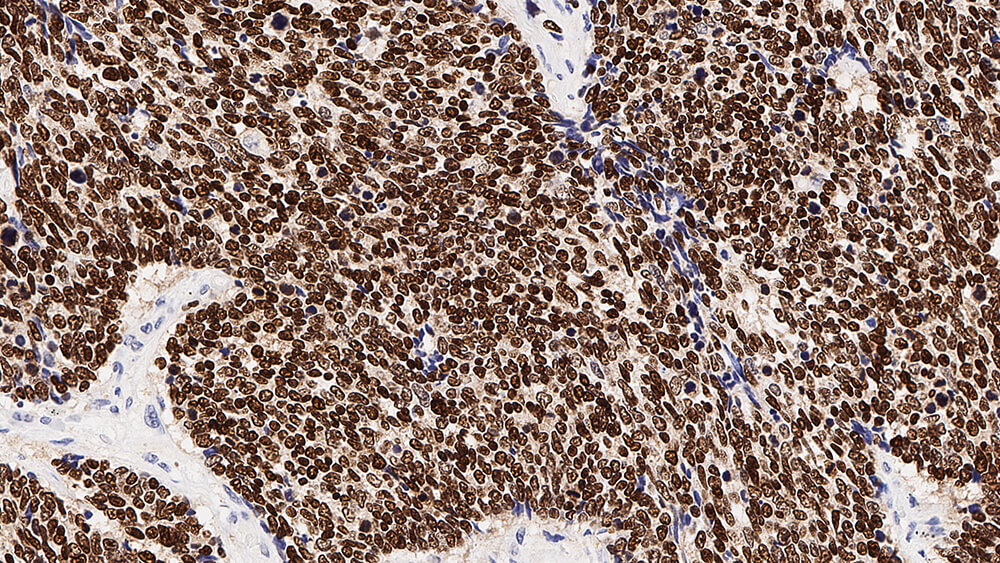

Thyroid Transcription Factor-1 (TTF-1) is a member of the homeodomain transcription factor family and plays a role in regulating genes expressed within the thyroid, lung and brain. These include thyroglobulin, thyroid peroxidase, Clara cell secretory protein and surfactant proteins. Human TTF-1 (38 kD) is a single polypeptide of 371 amino acids sharing 98% homology with the equivalent rat and mouse proteins. TTF-1 functions by binding to specific recognition sites in a manner that may be regulated by both the redox and phosphorylation status of the protein. In addition to its role as a tissue-specific transcriptional activator in adult organs, TTF-1 may also function in organogenesis. Gene targeting studies have shown TTF-1 to be essential for the proper development of the thyroid and lungs and abnormal expression may underline a number of congenital abnormalities.

Thyroid Transcription Factor-1 is recommended for the detection of specific antigens of interest in normal and neoplastic tissues, as an adjunct to conventional histopathology using non-immunologic histochemical stains.